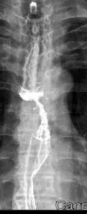

Patient XXX, male, 80 years old, began experiencing difficulty swallowing without obvious cause in February 2022, with progressive worsening. On January 22, 2023, he visited Zhangye People's Hospital, where an upper gastrointestinal contrast study revealed: mid-esophageal stenosis, approximately 5.5 cm in length, with concentric narrowing, mucosal disruption, and irregular filling defects and niches, suggesting mid-esophageal carcinoma (medullary type). On January 25, 2023, gastroscopy at Shanghai XX Hospital showed a circumferential mass protruding into the lumen at 26 cm from the incisors. Pathological examination after biopsy confirmed: (esophageal) squamous cell carcinoma. Upon admission to our hospital, the diagnosis was: 1. Malignant esophageal tumor (mid-esophagus, medullary type, squamous cell carcinoma, cT3N2M0, Stage IVB, KPS score: 90). After multidisciplinary team (MDT) discussion, the treatment plan was determined to be concurrent chemoradiotherapy: 1. Radiotherapy: Photon 40 Gy/20 fractions + carbon ion 16 Gy (RBE)/4 fractions; 2. Chemotherapy: Single-agent oral capecitabine chemotherapy.

Photon Volumetric Modulated Arc Therapy (VMAT) Plan Diagram

Before Radiotherapy During Radiotherapy After Radiotherapy